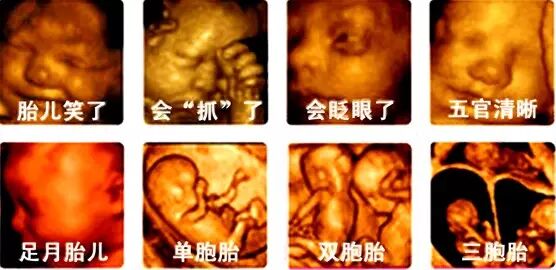

每个准妈妈都是兴奋和激动的,我家宝宝长什么样呢?是像他爸爸,还是像我呢?宝宝又动了,他在干什么呢?是自己玩呢,还是睡觉呢?是皱眉呢,还是笑呢?现在,四维彩超就可以给你一个准确的答案!这就是四维彩超带来的魅力,它能更清晰、更立体地把宝宝的一言一行,一举一动,生动地传达给孕妈妈,让孕妈妈和宝宝穿越时空提前相见

那么四维彩超单纯的只是给我们一张穿越时空的照片吗?当然不是!四维彩超能够多角度、多方位的观察胎儿在腹中的情况,还能对胎儿的体表进行检查,如唇裂,脊柱裂,大脑、肾、心脏、骨骼发育不良等情况,为早期筛查胎儿畸形提供重要依据,并且大大降低了各种畸形胎儿的出生率,已经成为目前排畸的一大利器。四维彩超来德保了,你约吗?

为什么说四维彩超是准妈妈的“4D”影院?四维彩超可称之为4D彩超,也就是四维成像技术,能直观、立体的显示人体器官的三维结构及动态、实时观察立体结构,具有即时立体成像、清晰准确的特点。

在这种情况下,四维彩超就展现了它强大的排查作用,四维彩超能够多方位、多角度地观察宫内胎儿的生长发育情况,能立体显示胎儿的颜色、面部轮廓及各器官的发育情况,甚至可以观察到胎儿在母体里的动作表情。为早期诊断胎儿先天性体表畸形和先天性心脏疾病提供准确的科学依据,最大限度的保障准妈妈生下健康的宝宝。